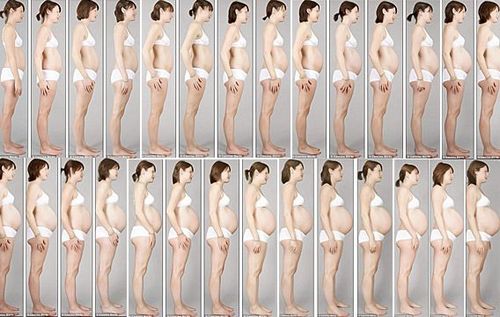

Починаючи з цього терміну, 32 тиждень вагітності, вага вагітної жінки може бути більше вже на 11 кг. Іноді, цей показник змінюється в більшу або меншу сторону, все залежить від організму мами і розмірів дитини. Висота розташування дна матки на 32 тижні дорівнює 32-33 см. А розмір живота у кожної майбутньої мами різний, він залежить від індивідуальних особливостей жінки. Якщо у вас 32 тиждень вагітності, фото животиків можете подивитися в Інтернет і порівняти зі своїм.